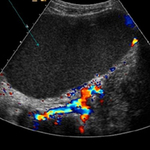

Ovarian cyst with normal Doppler flow

From the collection of Justin C. Chura, MD, Cancer Treatment Centers of America, Philadelphia, PA